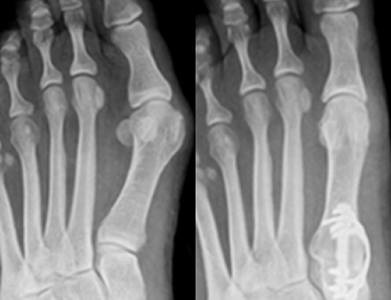

Arthrodesis for Bunions

Arthrodesis is typically a surgery that’s done on severe bunions and on people with arthritis. Your doctor will remove the affected joint surfaces and then rely on plates, screws, and possibly wires to hold bone together around the removed joint until the bones have a chance to heal.

Osteotomy Surgery for Bunions

An osteotomy can be performed for other conditions, not just bunions. The term osteotomy refers to any surgery where bones are reshaped, but when talking about bunions, an osteotomy is performed to remove a bit of bone to help realign the toe and support the joint. Typically, pins and screws will be used to support the newly aligned bone and to keep the toe straight.